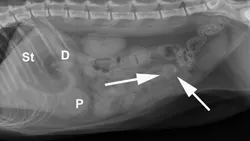

Radiographic Findings: The stomach (St) and duodenum (D) are severely distended with fluid and gas, suggesting intestinal obstruction or possibly pancreatitis with secondary ileus.

There is a 1.5-cm rounded opaque structure (arrows) in the caudal abdomen, to the left of the descending colon on the VD view. It is partially obscured by feces in the colon (C) on the left lateral view. The remaining organs and serosal detail appear normal.

A radiograph of a canine abdomen shows the digestive organs, labeled with 'P' for pancreas, 'St' for stomach, and 'D' for duodenum. An arrow points to a notable mass in the lower abdomen, indicating a potential clinical concern.

Comments: We often perform left and right lateral radiographic views of the abdomen in cases of suspected GI foreign bodies and obstructions since the fluid and gas disperse into different portions of the GI tract. For example, any gas in the stomach rises to the pylorus (P) in left lateral recumbency and may outline a foreign body anchored to this region; this is particularly useful in suspected linear foreign bodies, which typically anchor to the tongue or pylorus and subsequently plicate varying degrees of small intestine.